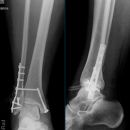

Sprunggelenk

Weber A

Weber B

Weber C + dorsales Volkmann

Trimalleoläre

Vorderes Volkmann + lat. Talusschulter